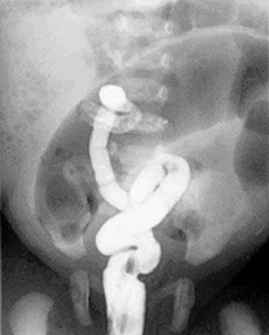

Pediatric Radiology > Abdominal > Neonatal > Meconium Ileus - Radiographic Features

Meconium Ileus - Radiographic Features

Microcolon (unused colon) · "Frothy" or "soap-bubble" pattern of bowel gas (air mixed with meconium), often in the right lower quadrant · Dilated small bowel loops · Small bowel obstruction · Calcification due to meconium peritonitis (15%) · Distal ileum packed with meconium and larger than microcolon on contrast enema |